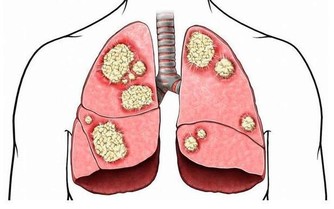

當慢性淺表性胃炎發展為慢性萎縮性胃炎時,胃黏膜常伴有腸上皮化生,也就是說胃里長出了本該在腸道才有的細胞,而且正常胃黏膜的分泌功能改變為腸道的吸收功能。由於胃黏膜對吸收的東西無法解毒,天長日久,在部分患者胃內局部形成致癌物質,因此“腸上皮化生”又被稱為癌前病變。

近年來

“腸上皮化生”的患者越來越多,已佔胃腸病患者的一兩成,而且有年輕化趨勢,尤其是在精神壓力較大的都市白領人群中更明顯,這和飲食不規律、壓力大等都可能有關。

臨床統計結果表明,部分“腸上皮化生”會發展為胃癌,但正常人的胃裡也會有“腸上皮化生”,因此不必過分緊張,但應引起足夠重視。